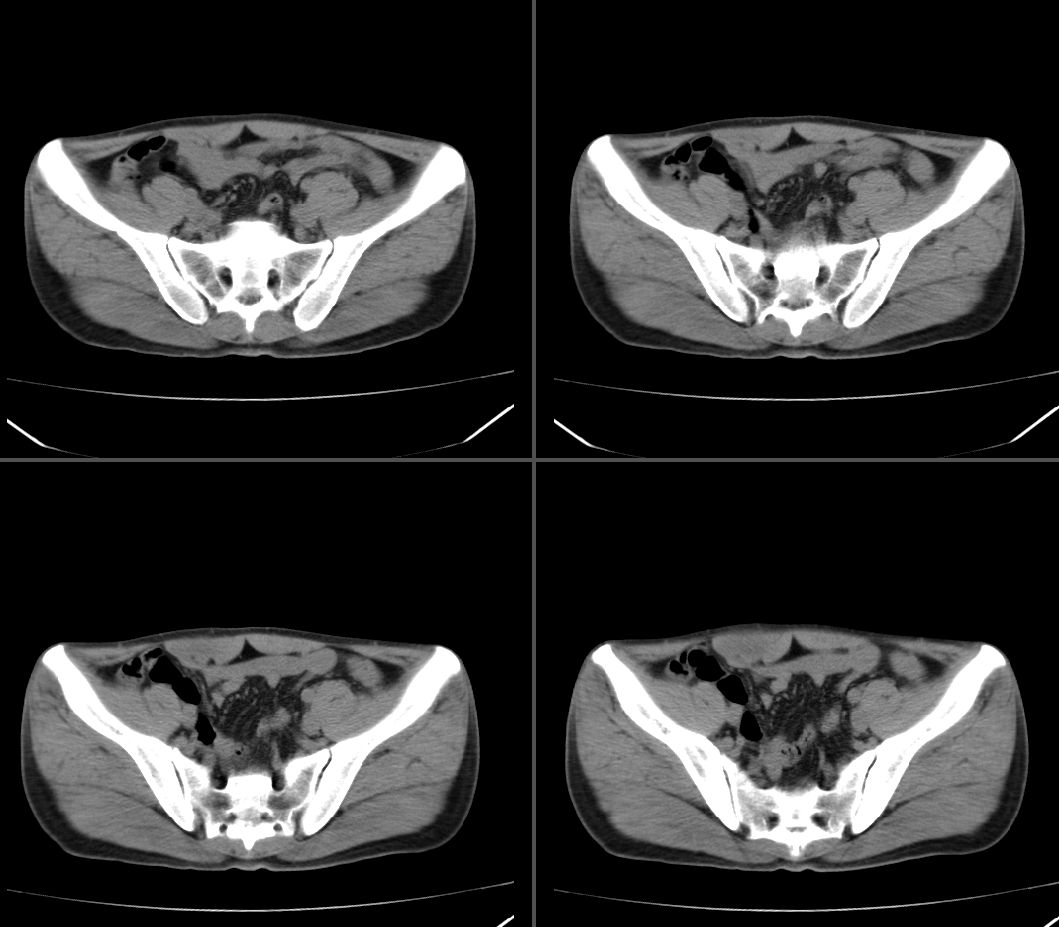

定位:右腹直肌鞘下部

病灶特点:分界清,边缘光整,囊性密度,病灶成长椭圆形,病灶处腹直肌受压萎缩,病灶与膀胱处有相似密度管状灶(该征象因肠道未作准备,不能确切)

右腹直肌腱鞘来源,韧带样纤维瘤可能性大,病变有侵袭性,右侧耻骨联合有骨质缺损。

前腹壁肿块,囊性变,右侧耻骨联合有骨质缺损。

右腹直肌腱鞘来源,耻骨联合有骨质缺损,考虑神经源性肿瘤